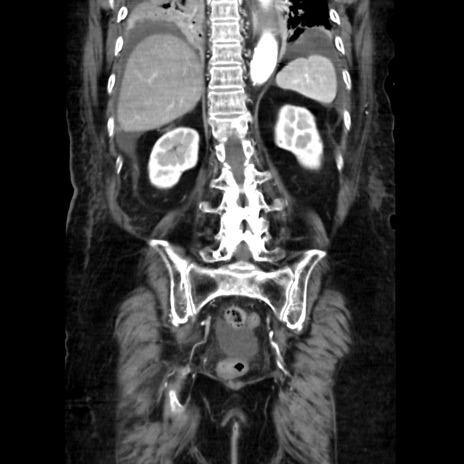

【症例】90歳代女性

【主訴】腹痛・嘔吐

【現病歴】 食欲低下、嘔吐があり昨日他院受診。肺炎と診断され入院となる。入院後より腹部全体に圧痛あり。胃管留置され経過みていたが、症状持続するため、

当院転院となる。

【既往歴】胸椎圧迫骨折、胆石症

【身体所見】腹部:中央に激痛あり、圧痛あり、反跳痛不明

【データ】WBC 17100、CRP 18.82

冠状断像